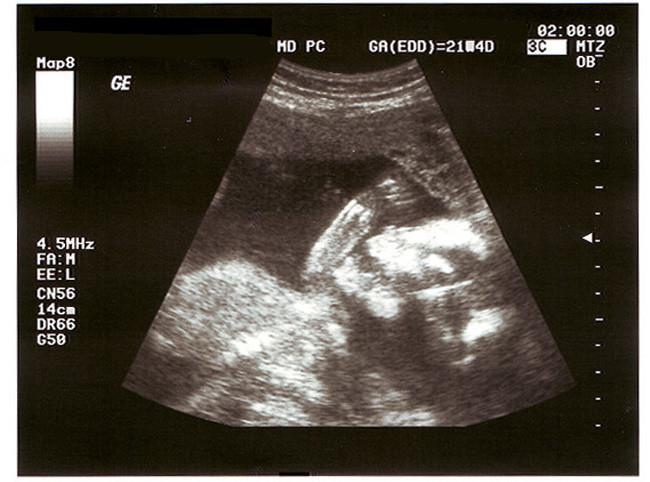

El análisis de vellosidades coriónicas (CVS) se realiza de forma transcervical, es decir a través del cuello del útero o si no fuese accesible, a través de una punción abdominal con anestesia local. A la vez, se realiza una ecografia, que permite visualizar las estructu­ras maternas y fetales para asegurar que la biospia se hace bien y sin problemas.

Se realiza en torno a la semana 15 de gestación y consiste en extraer mediante una punción abdominal una muestra del líquido amniótico que rodea al feto.